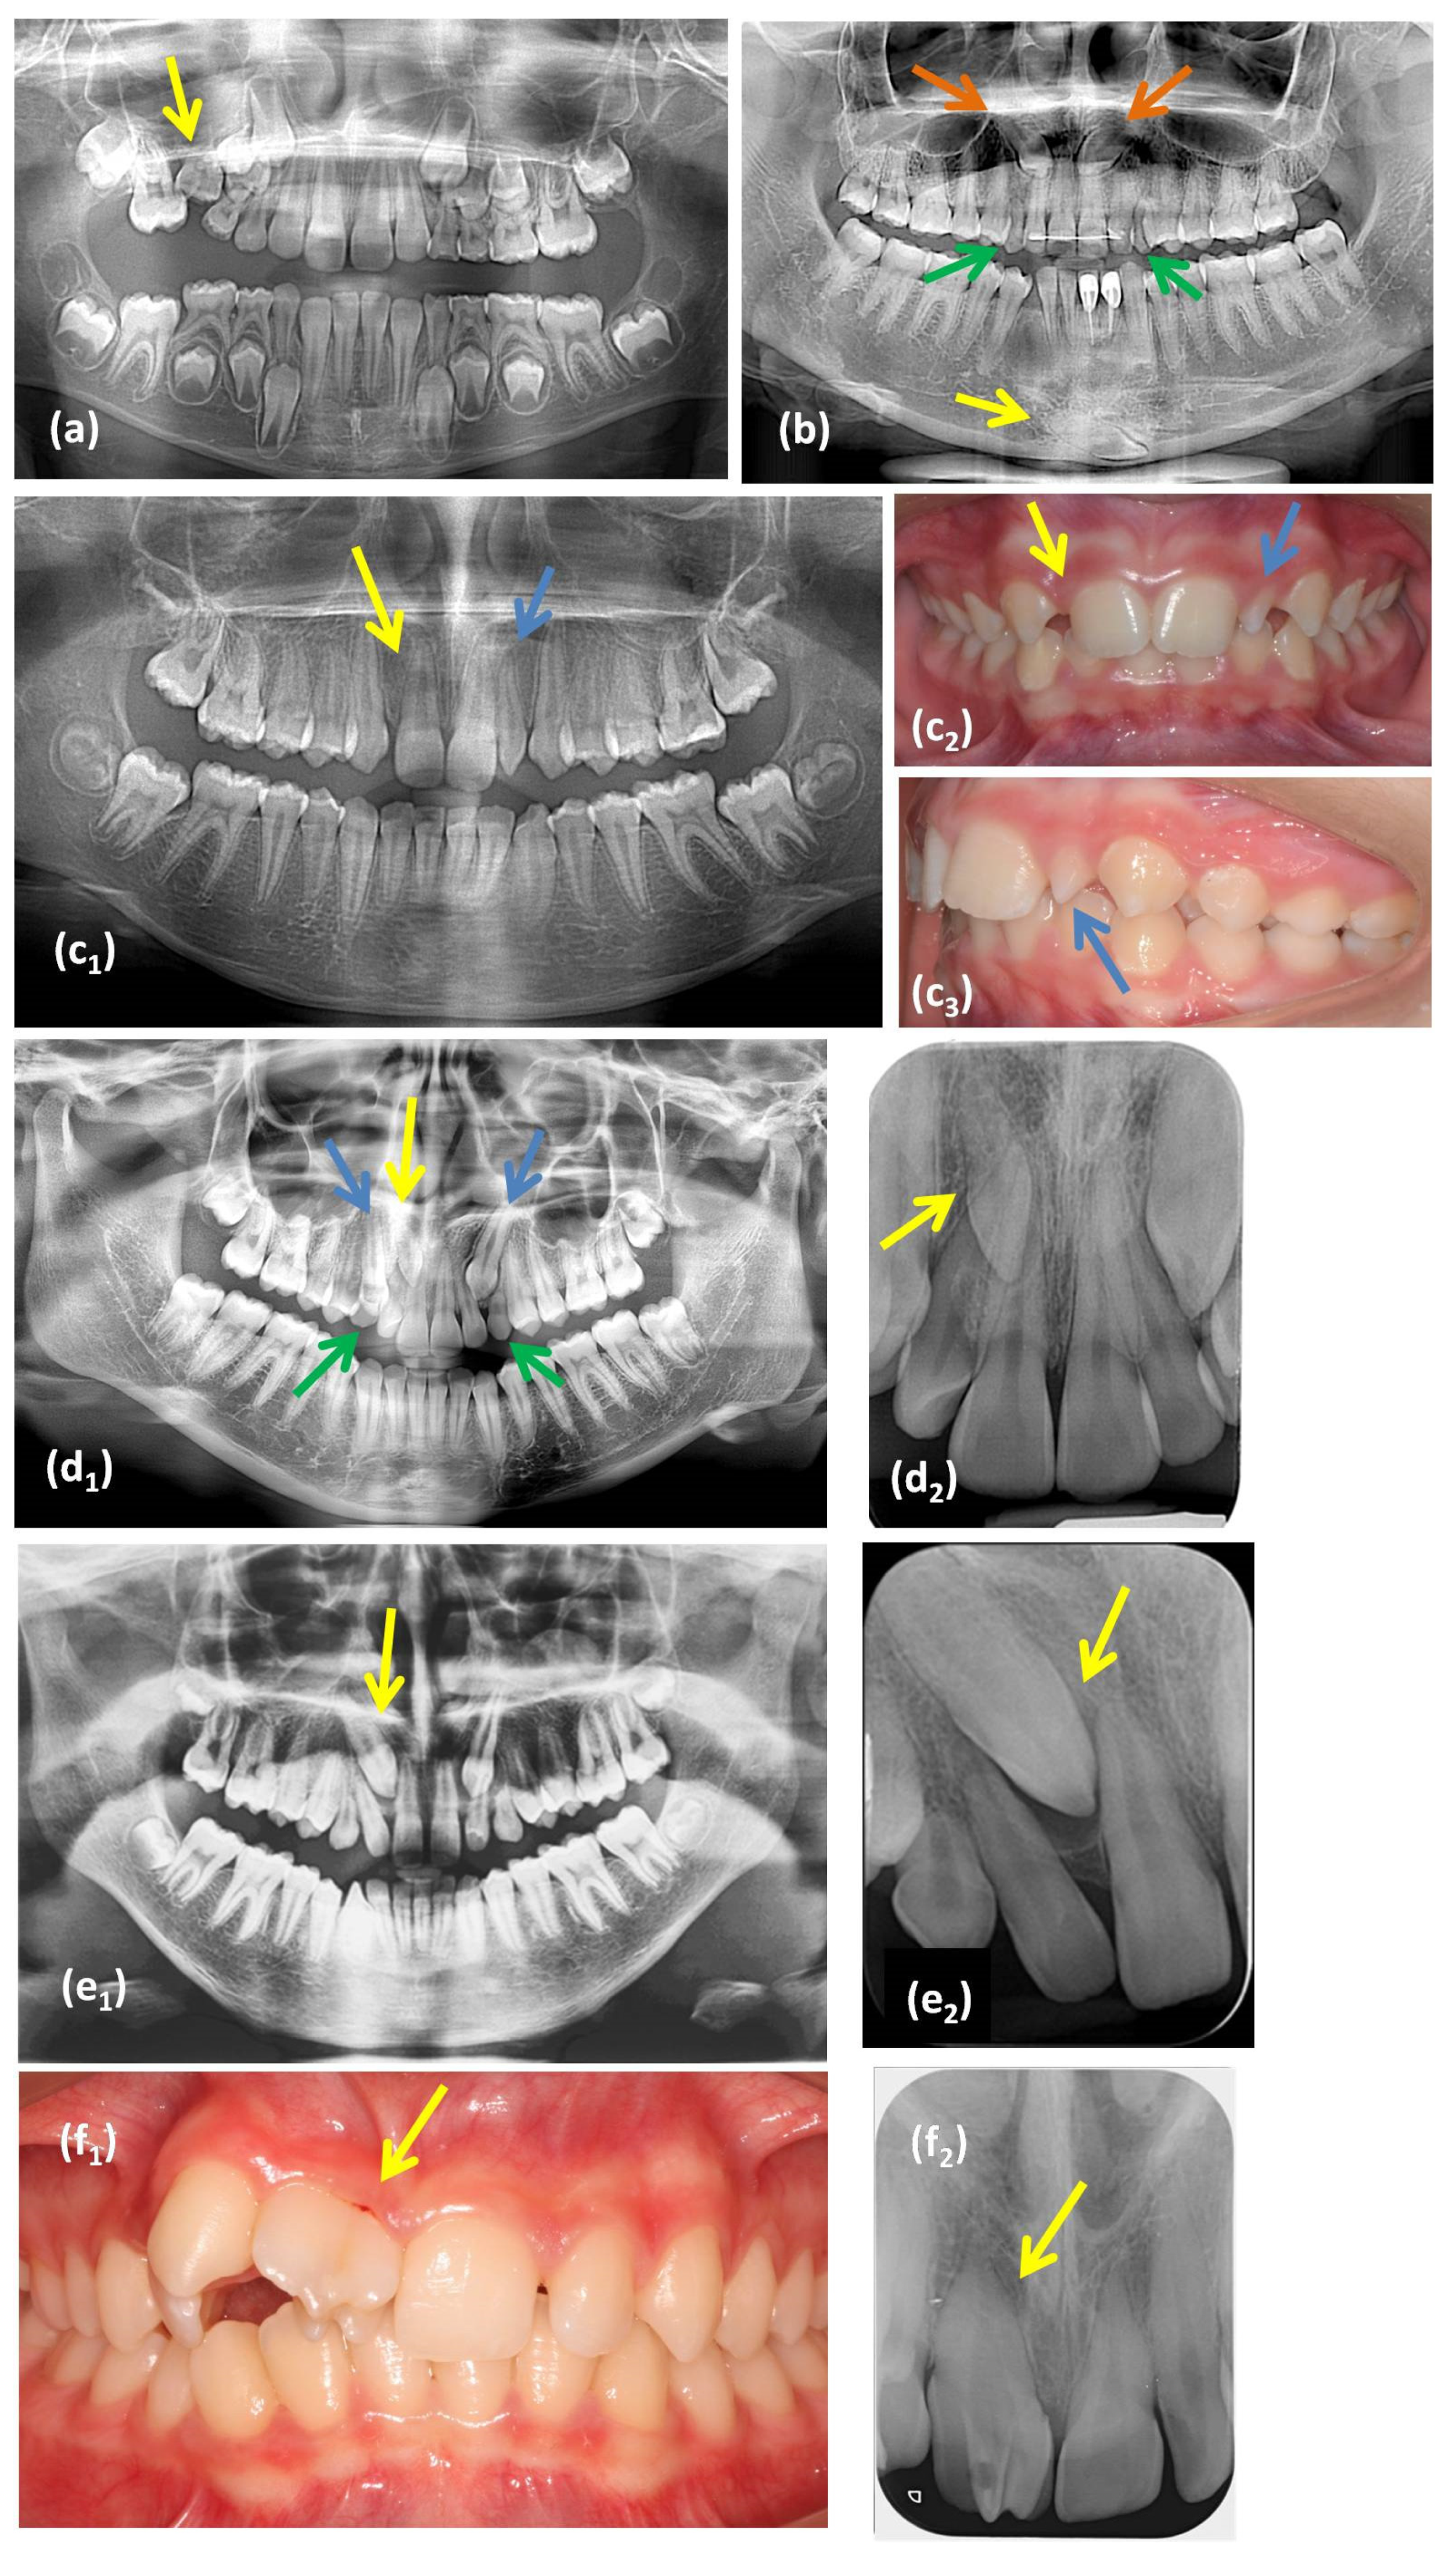

Eleven dental anomalies, divided into four categories (number, size and shape, position, and eruption), were considered in the study. Their diagnostic criteria appear in Table 1 and Figure 1.

Figure 1.

Examples of dental anomalies evaluated on radiographs and intraoral photographs: (a) panoramic radiograph of a patient with a submerged tooth #55 (yellow arrow); (b) panoramic radiograph of a patient with maxillary impacted canine teeth #23 and 13 (orange arrows), retained deciduous canine teeth #53 and 63 (green arrows), and a mandibular canine transmigration tooth #43 (yellow arrow) located at the lower border of the symphysis; (c) an example of a patient with a missing tooth #12 (yellow arrow) and a peg-shaped incisor tooth #22 (blue arrow): (c1) panoramic radiograph, (c2) intraoral frontal photograph, (c3) intraoral lateral photograph; (d) an example of a patient with a supernumerary tooth (impacted between the roots of the teeth #11–12, yellow arrow), impacted canine teeth #13 and 23 (blue arrows), and retained deciduous teeth #53 and 63 (green arrows): (d1) panoramic radiograph, (d2) periapical radiograph; (e) an example of a patient with dental transposition of the teeth #13 and #12 (yellow arrow): (e1) panoramic radiograph, (e2) periapical radiograph; (f) an example of a patient with fusion of the teeth #11 and 12 (yellow arrow): (f1) intraoral photograph, and (f2) periapical radiograph.